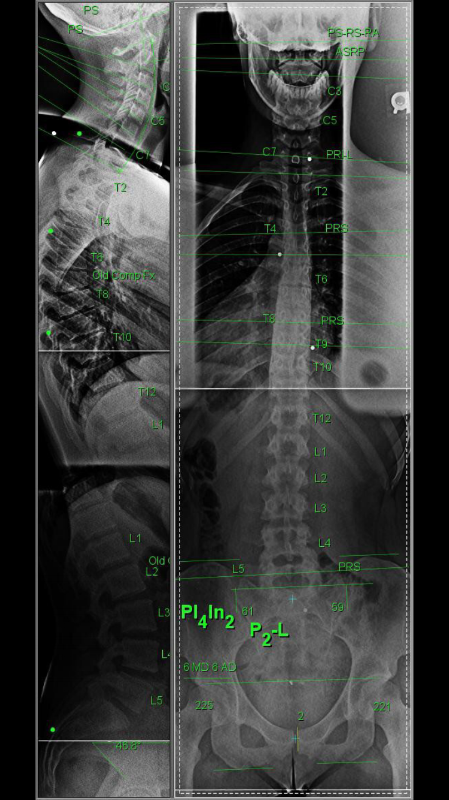

The Gonstead Method is a highly specific chiropractic system developed to analyze and correct spinal and joint dysfunction with unmatched precision. Unlike generalized adjustments, Gonstead care is segment-specific, meaning only the exact problem areas are addressed.

Key components of Gonstead analysis include:

- Postural assessment

- Motion palpation

- Static palpation

- Neurological evaluation

- Digital X-ray analysis (when clinically necessary)

This level of detail allows a chiropractor to determine which vertebra or joint is causing nerve interference, how it affects movement, and how it contributes to pain or injury.

Your sports injury assessment may include:

- Detailed injury history and training habits

- Postural analysis to identify imbalances

- Joint motion testing to locate restrictions

- Neurological evaluation for nerve involvement

- Digital X-rays if structural assessment is needed